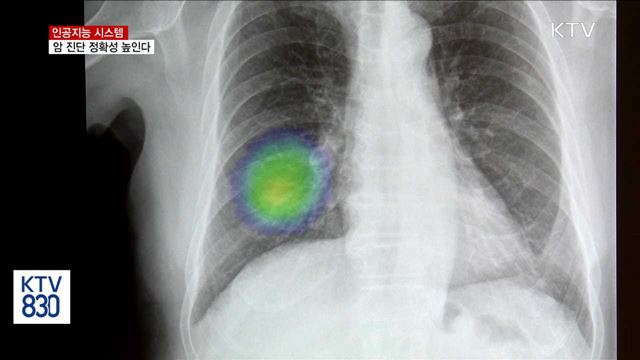

인공지능 시스템, 암 진단 정확성 높인다

다양한 분야에서 인공지능을 활용한 연구 개발이 활발합니다. 양성종양을 정확하게 판독해서, 암을 일찍 발견하도록 돕는 인공지능 시스템이 주목받고 있습니다. 박천영 기자입니다. 폐암 초기 환자의 X-ray 촬영본입니다. 18명의 영상의학과 전문의에게 판독을 의뢰했는데 18명 모두 해당 환자의 종양을 발견하지 못했습니다. 종양의 위치가 뼈에 가려져 ...